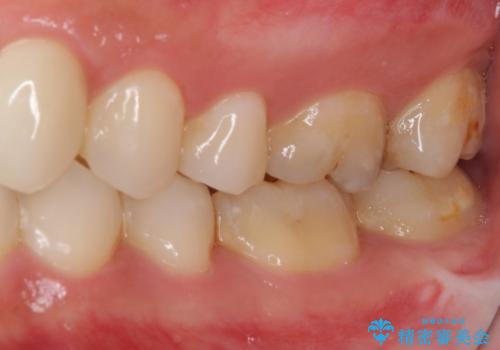

- 審美的ではない上の前歯とデコボコの下の前歯、歯茎が腫れている奥歯を気にして来院された患者様です。

根管治療の必要な歯がいくつかあるため、まずは根管治療を行い、その後インビザラインにて矯正治療を行うこととしました。

矯正治療後に前歯をセラミックブリッジに、奥の銀歯はセラミックインレーやPGAインレー(ゴールドインレー)にて補綴・修復治療を行うこととしました。